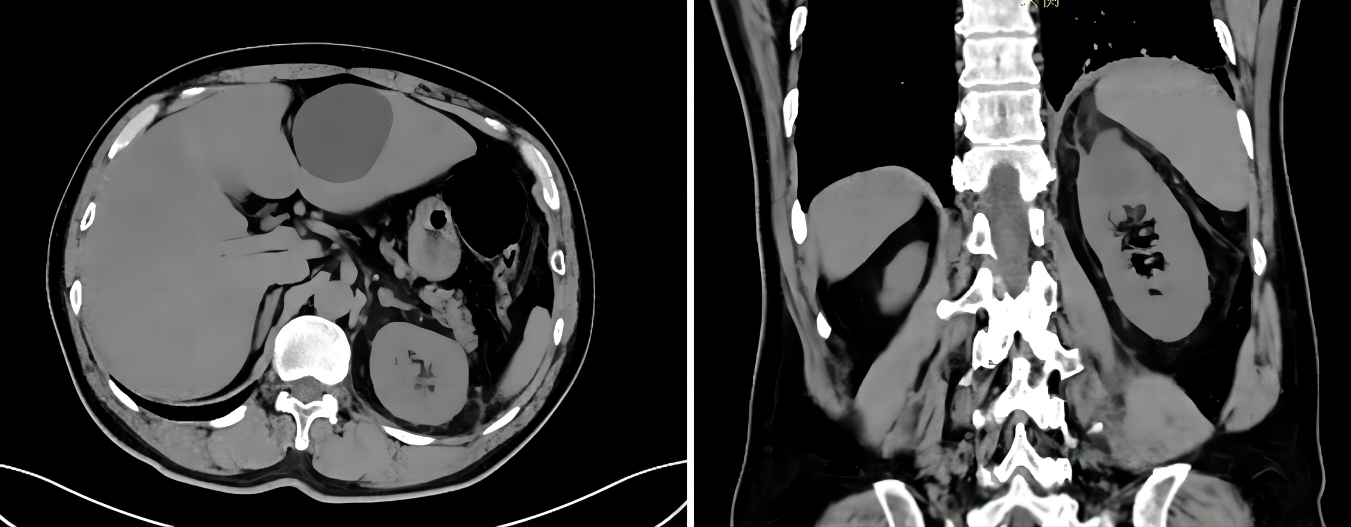

现病史:患者1天前在无明显诱因下出现发热,最高达39.9℃,伴畏寒寒战,乏力纳差,无胸闷气急等不适,自行口服“退热药”(具体不详),后患者体温持续波动于39~40℃,仍感乏力纳差,无畏寒寒战、胸闷气急,为进一步诊治就诊于我院。2023-09-14门诊CT(胸部平扫+全腹部)显示:左膈面升高伴左肺下叶局部盘状不张、炎性纤维灶,左肾上极低密度灶伴周围渗出,建议进一步检查,左肾周筋膜增厚,附见两侧胸膜增厚(图1)。拟“发热待查”收治入科。患者自发病以来,神清、精神可、胃纳差、二便无殊、近期体重变化不详。

图1. 门诊CT(胸部平扫+全腹部)检查

2023-09-16 CT(全腹平扫+增强)显示:1. 左肾上极囊肿伴感染考虑,建议短期复查;2. 脂肪肝,多发肝囊肿,两肾囊肿;3. 胆囊腺肌症考虑;4. 胰尾部囊性灶,建议复查;5. 前列腺增生、钙化。

调整用药方案后,患者未再发热,CRP持续下降,由89.1 mg/L(2023-09-18)下降至20.5 mg/L(2023-09-21)。2023-09-21患者家属要求停用依拉环素,停用后患者CRP出现反弹,次日升至46.9 mg/L,予改回依拉环素治疗至足疗程(7天),改回后患者CRP再次下降至17.8 mg/L(2023-09-24)。2023-09-25复查增强CT,左肾上极囊肿伴感染较前(2023-09-16)好转(图3)。

图3. 增强CT检查(左:2023-09-16,右:2023-09-25)